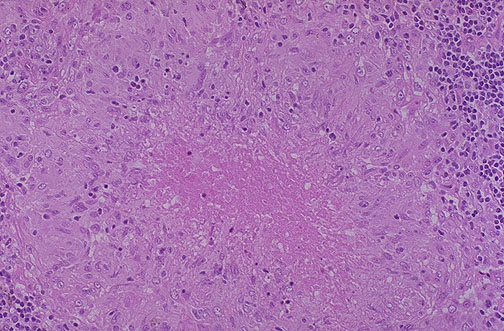

This is a caseating granuloma. Epithelioid cells surround a central area of necrosis that appears irregular, amorphous, and pink. Grossly, areas of caseation appear cheese-like.